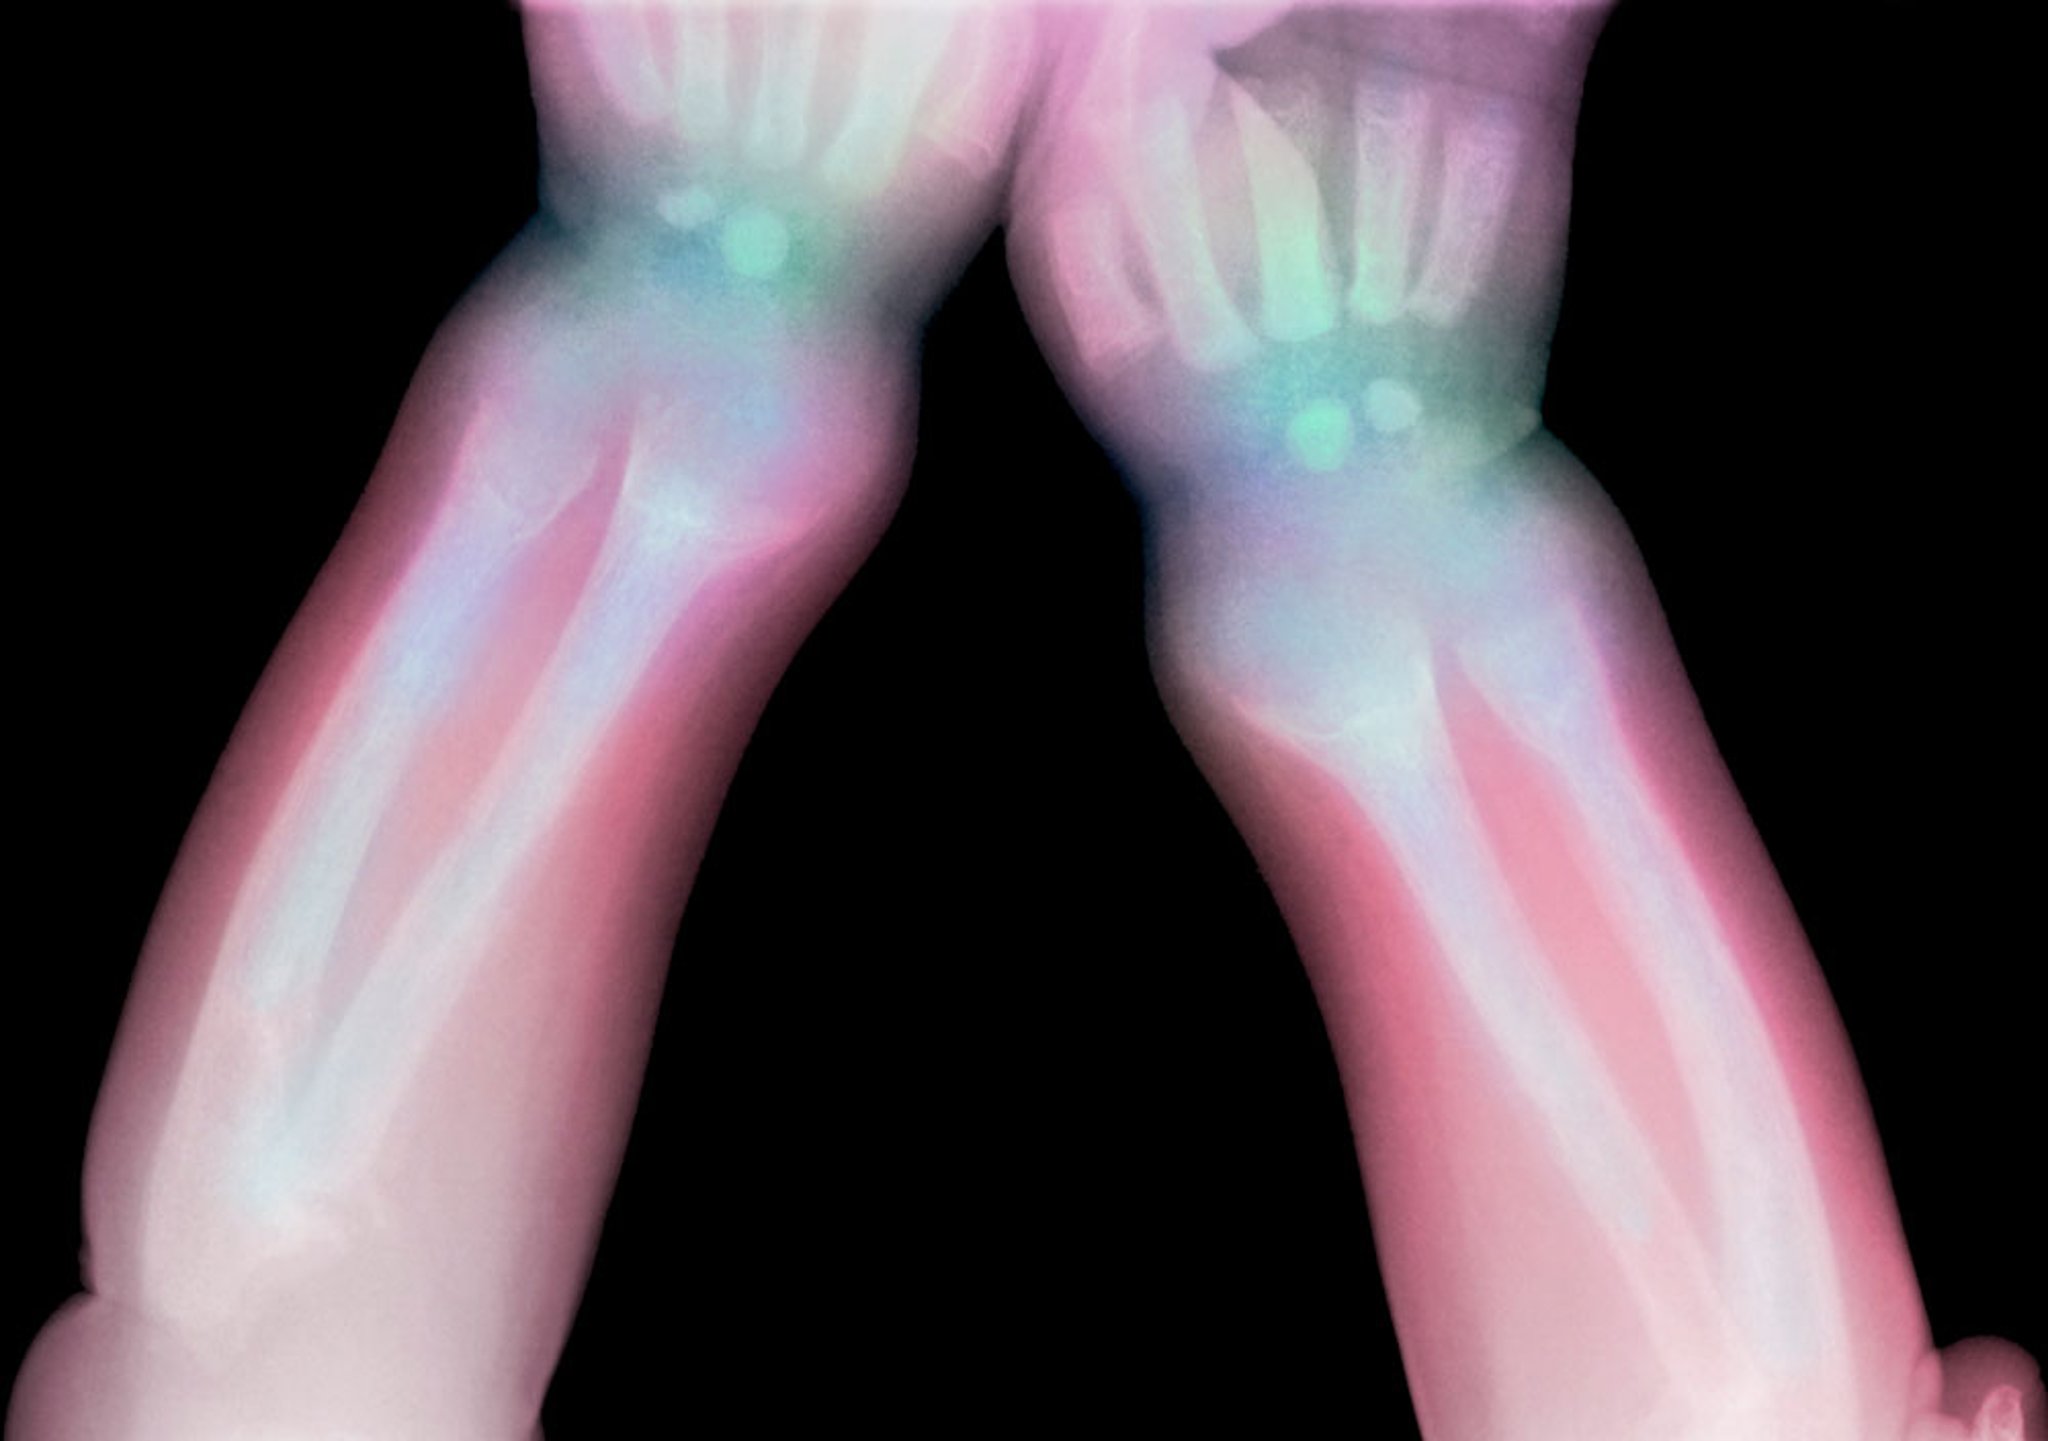

Essa radiografia mostra a lucência do rádio distal e da ulna em uma criança com raquitismo.

Credit DU CANE MEDICAL IMAGING LTD / SCIENCE PHOTO LIBRARY